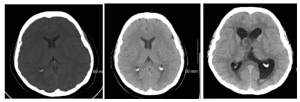

The left lateral ventricle was moderately enlarged. Multiplanar magnetic resonance imaging was significant for a large 4.6 x 4.3 x 2.9 cm mass extending from the foramen of Monro, occupying the entire anterior aspect of the lateral ventricles (Figure 2). CT of the chest, abdomen, and pelvis was negative for any other masses. The patient had some complaints about back pain. The entire neuroaxis was scanned, as a primary intraventricular tumor was also in the differential.

Figure 2: (A) Non-contrast axial T1 MRI (B) Axial T1 MRI with contrast (C) T2 axial MRI without contrast